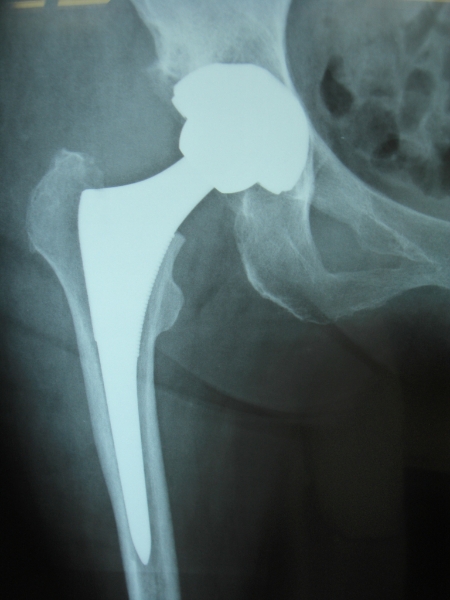

50歳 変形性股関節症 MIS-DAによる人工股関節置換術

術後3日目に歩行訓練開始し術後2週で杖なし歩行で退院

58歳 大腿骨頭壊死 MIS-DAによる右人工股関節置換術

術後2日で離床、3日めに歩行器歩行訓練開始、5日で杖歩行、7日で杖なし歩行可能となり2週で退院

86歳 続発性変形性股関節症 MIS-DAによる右人工股関節置換術

術後3週で杖歩行により退院